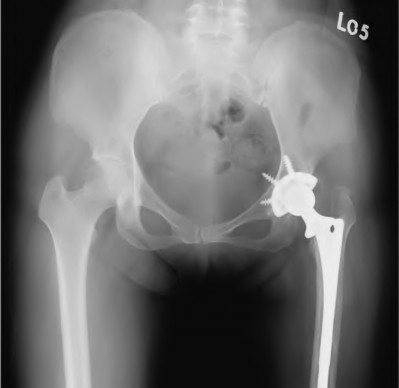

Question 9:

A 55-year-old highly active man is scheduled for a total hip arthroplasty (THA). The surgeon considers utilizing a ceramic-on-ceramic bearing surface to maximize longevity. Which of the following is the most notable disadvantage or complication specific to a ceramic-on-ceramic bearing compared to ceramic-on-highly cross-linked polyethylene?

Correct Answer: Audible squeaking during hip articulation

Explanation:

Ceramic-on-ceramic (CoC) bearings offer the lowest wear rates of all THA bearing couples and do not cause significant osteolysis or metal-related hypersensitivity. However, a well-documented unique complication of CoC bearings is audible squeaking during motion, occurring in up to 10-15% of patients in some series, often associated with micro-separation or impingement.